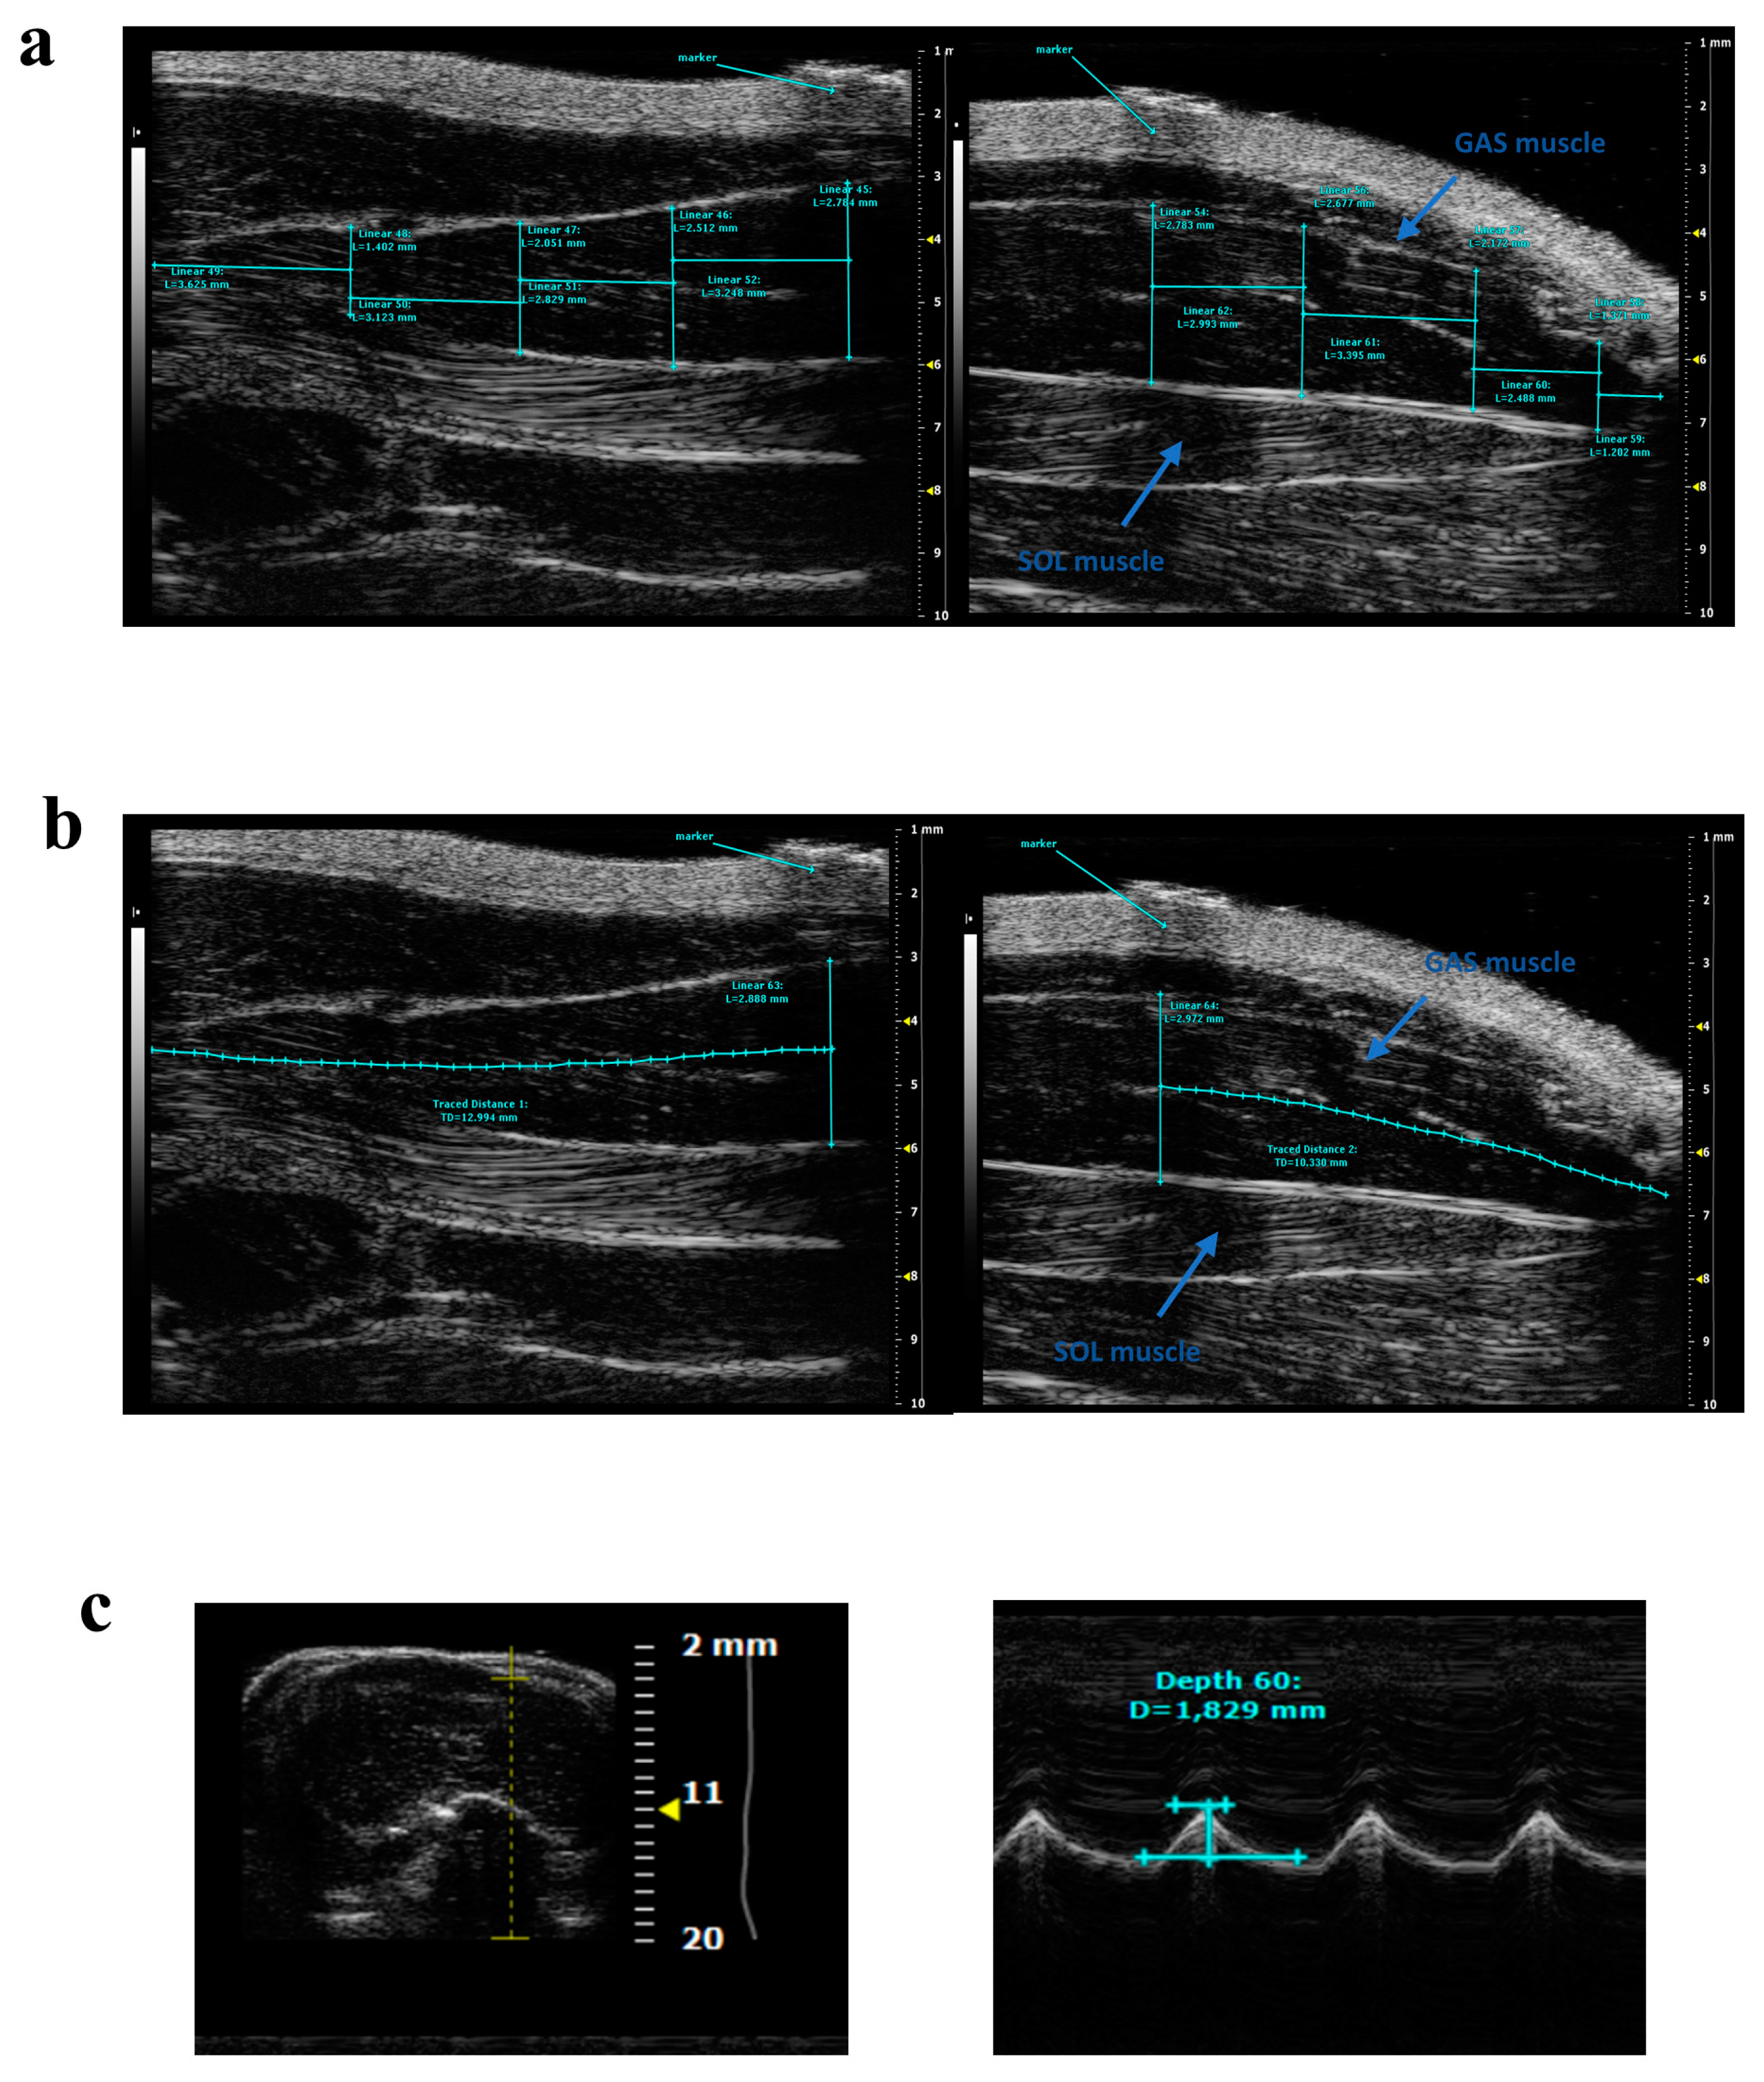

| Vevo 770 (VisualSonics, Toronto, ON, Canada) 40 MHz | GAS, SOL | Rat in ventral decubitus position with the ankle immobilized in full extension. Longitudinal acquisitions | PA, MT | [22] |

| Vevo 770 (VisualSonics, Toronto, ON, Canada) 40 MHz | GAS | Rat in ventral decubitus position with the ankle immobilized in an angle of 90°. Longitudinal acquisitions | PA, MT | [25] |

| Vevo 2100 (VisualSonics, Toronto, ON, Canada) 40 MHz | GAS, SOL | Rat in ventral decubitus position, with the hind limbs parallel to the body and with the foot forming an angle of 90° with respect to the hind limb, placing the probe parallel to the longitudinal muscle axis | Volume | [23] |

| Vevo 2100 (VisualSonics, Toronto, ON, Canada) 40 MHz | FDL | Rat in dorsal decubitus position, with the hind limb at its maximum extension and strictly parallel to the rat body, placing the probe parallel to the longitudinal muscle axis | Volume | [30] |

| Vevo 2100 (VisualSonics, Toronto, ON, Canada) 21 MHz | Hind limb | Mouse in ventral decubitus position, with the hind limbs parallel to the body and with the foot forming an angle of 90° with respect to the hind limb, placing the probe parallel to the longitudinal muscle axis | Volume and echodensity | [24,31] |